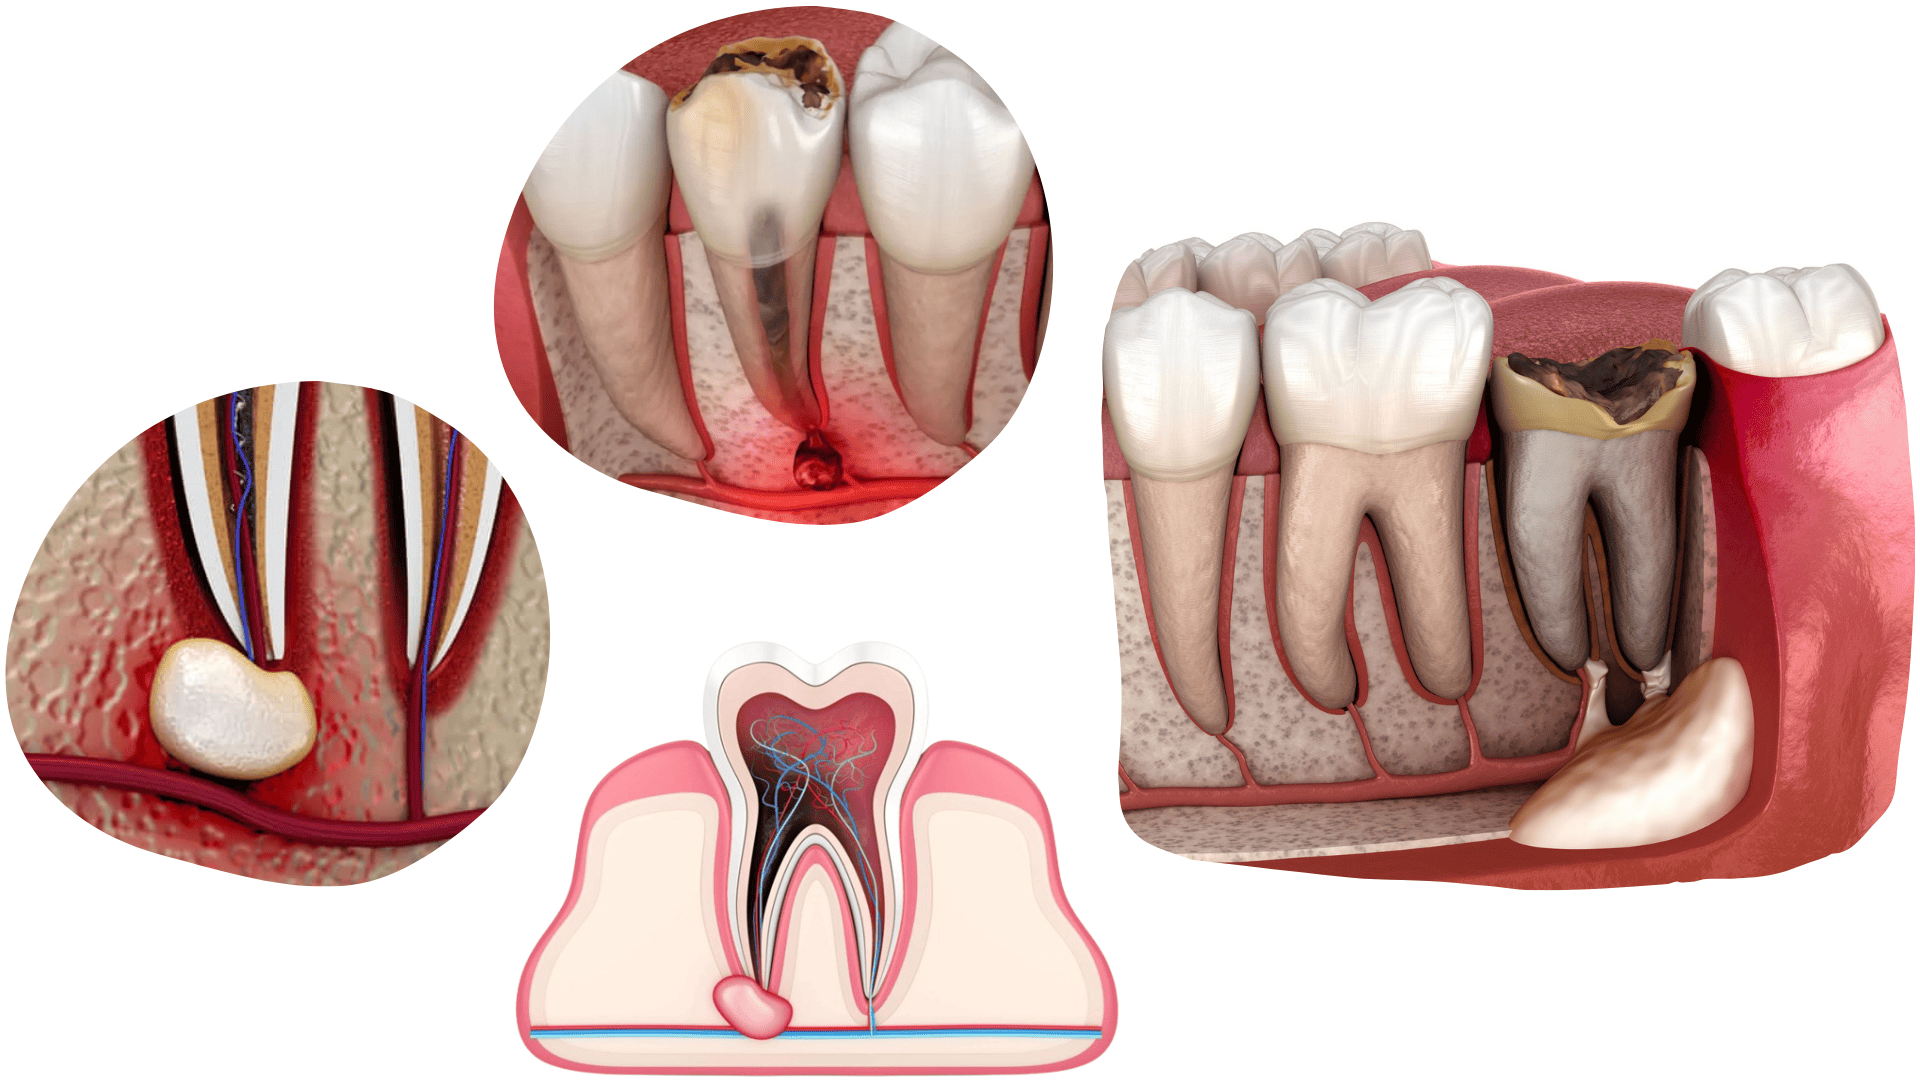

APIKOTOMIJA

Apikotomija je oralno-kirurški zahvat kojim se uklanja vrh korijena zuba koji ima upalni proces.

Apikotomiju radimo kod onih zubi kojima endodoncija nije pomogla riješiti upalni proces na vrhu korijena.

Apikotomija je kratak i bezbolan zahvat koji se izvodi u lokalnoj anesteziji.

CISTEKTOMIJA

Cistektomija je kirurški zahvat uklanjanja periapikalnih lezija poput apscesa, granuloma ili različitih cisti oko korijena zuba.

Ove promjene najčešće se otkriju na ortopan snimci kada pacijent dođe zbog jakih bolova ili oteklina. Ciste nastaju kao posljedica kronične upale ili neuspješne endodontske terapije.

Zahvat se izvodi pod lokalnom anestezijom, bezbolan je i omogućuje brz oporavak.